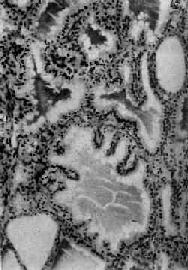

肉眼观,甲状腺对称性弥漫肿大,一般为正常的2~4倍,质较软,切面灰红,胶质含量少。镜下,以滤泡增生为主要特征,滤泡大小不等,以小型滤泡为主。小型滤泡上皮呈立方形,大型滤泡上皮多为高柱状,常向腔内形成乳头状突起。滤泡腔内胶质少而稀薄,胶质的周边部即靠近上皮处出现大小不等的空泡,有的滤泡内甚至不见胶质。间质中血管丰富,显著充血,有多量淋巴细胞浸润并有淋巴滤泡形成(图15-7)。经碘治疗的病例,由于碘能阻断含甲状腺素胶质的分解和促进胶质的储存,故胶质增多变浓,上皮增生受抑制,间质充血减轻,淋巴细胞也减少。与此相反,经硫脲嘧啶等阻断甲状腺素合成的药物治疗者,由于血中TSH代偿性增加,故滤泡增生更明显,上皮呈高柱状,胶质更稀少甚至消失。

图15-7 毒性甲状腺肿

滤泡增生,有的扩大,上皮呈立方或高柱状,并乳头状突起。滤泡腔内胶质稀薄,周边有大小不等空泡